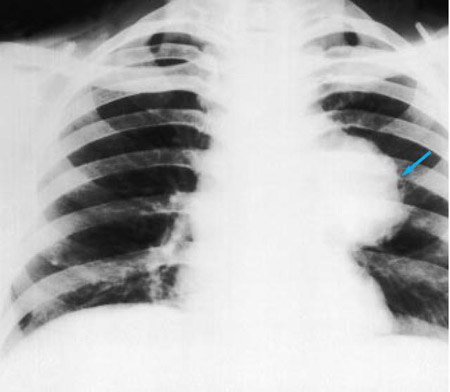

Radiografía de tórax que muestra un carcinoma hiliar izquierdo (flecha)

De: E. Dick, Student BMJ. 2000;8:358-360